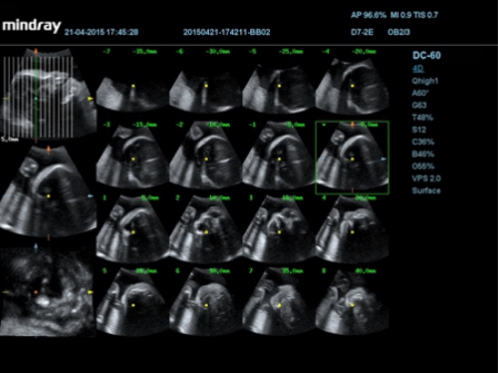

Smart OB?

Auto measurement of fetal parameters: trace and calculate the BPD, OFD, HC, AC and FL on a single click.